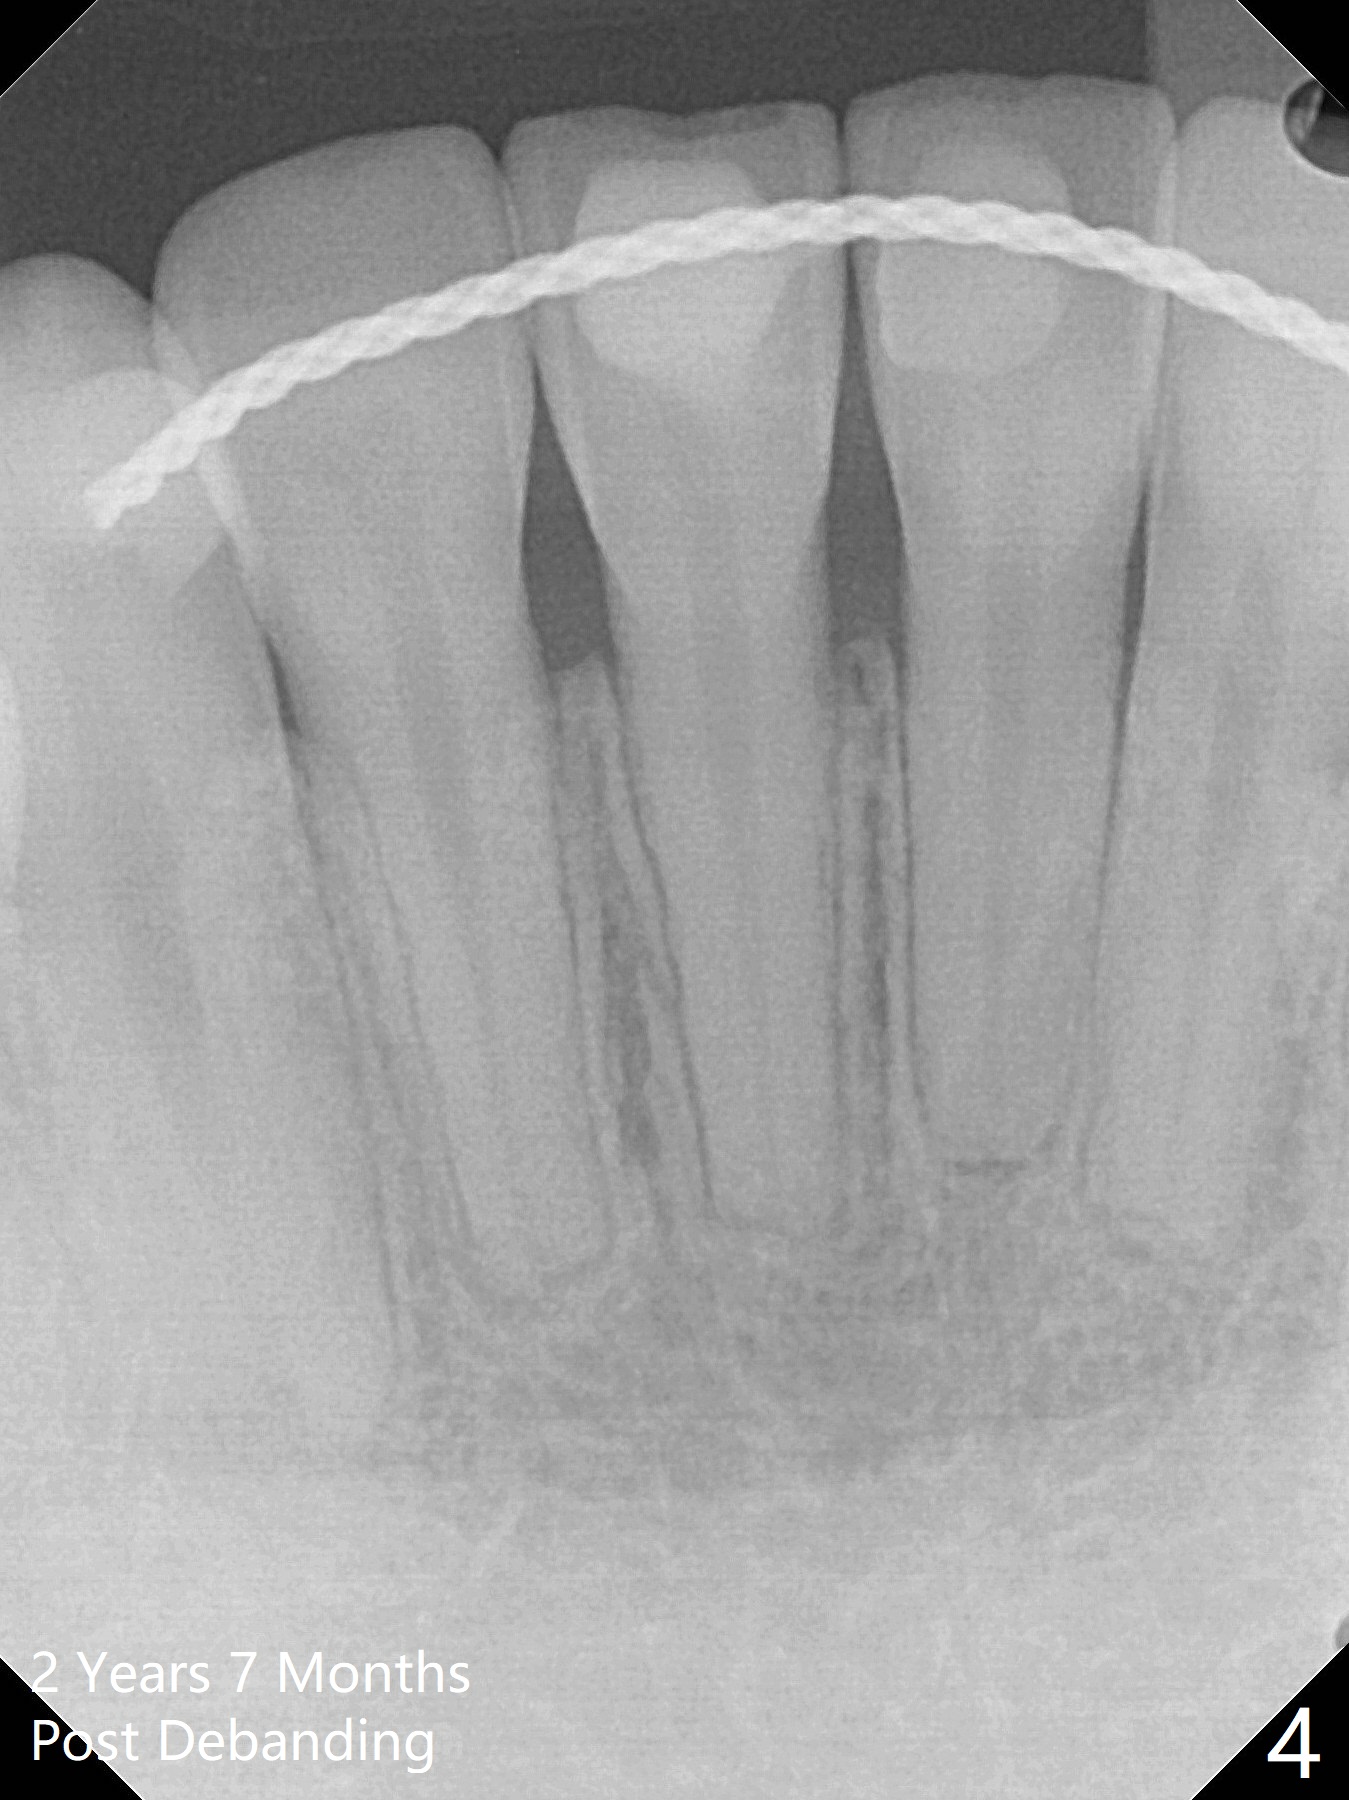

2 Years 7 Months Post Debanding

Return to Ortho Cases 植牙,导板与正畸 Five months post debanding 3 Years Post Debanding